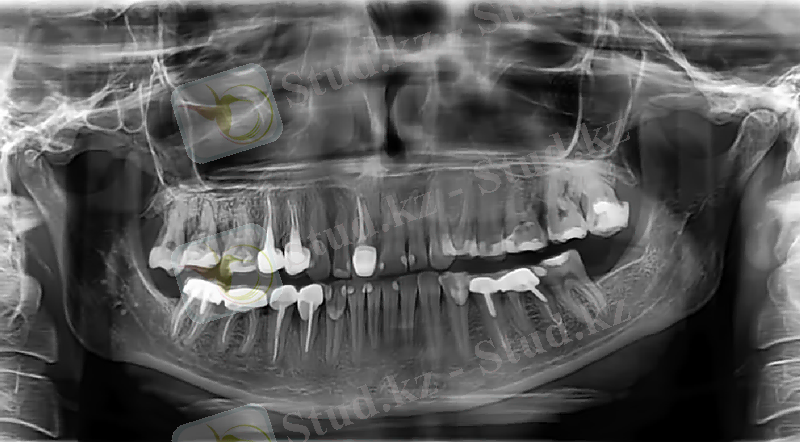

Балаларда пульпитті емдеу тәсілін таңдауда тұрақты және сүт тістердің түбірлерінің сорылу мерзімін ескеру керек. Сүт тістердің түбірлерінің толық қалыптасуы сүт тістер түбірлерінің қалыптасып болғаннан кейінгі 3-4 жылдан соң және шығып болғаннан кейін 4-5 жастан соң аяқталады. Балаларда жұқпалы аурулармен ауырған немесе созылмалы аурулармен асқынған тұрақты тіс түбірінің қалыптасуы олар шыққаннан кейінгі 5-6 жастан кейін (кейде 7 жаста) аяқталады

Рентгендік тексеру емдеу әдісін дұрыс таңдау мен сол арқылы асқынулардың алдын алуға мүмкіндік береді. Тістердің түбірлерінің қалыптасу және сорылу мерзіміне сүйене отырып пульпитті емдеуде көрсетілімдерді таңдауда мышьяк пастасын қойғаннан кейінгі перипикалды аймақта әр түрлі асқынулардың алдын алу үшін сүт азу тістерін 8-9 жаста жұлу керек. Сүт күрек тістерде пульпит некроз және ұлпаның өлуі салдарынан өте сирек кездеседі. Олар созылмалы периодонтитпен асқынады. Ұлпа қабынуын емдеу әдісін таңдауда бірінші кезекте қабынудың таралуы және түбір өзегін сипаттайтын анатомиялық талаптан кейін тістің жағдайын және баланың жалпы жағдайы маңызды болып табылады. Ұлпаны жасанды некрозды шақырып немесе иньекционды жансыздандыруды қолданып жансыздандырады (ұлпа қабынуын девиталды және виталды емдеу әдістері) .

Эндодонтиялық араласулар мына жағдайларда міндетті:

• 9 жастағы төмен орталық және бүйір күрек тістер үшін

• 12 жасқа дейін төменгі үшкір тіс және І кіші азу тістер үшін

• 13 жасқа дейінгі 2 премолярға және 14 жасқа дейінгі жоғарғы үшкір тістер және екінші үлкен азу тістер үшін. Бұл өсу аймағының сақталуын қамтамасыз етеді.